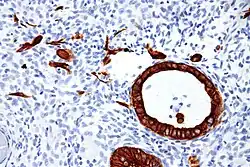

- Chorionic-type intermediate trophoblast[1]

- round to polyhedral nuclei, may multinucleation

- abundant eosinophilic to clear cytoplasm

- cohesive growth

- Placental site nodule (PSN): chorionic-type IT

- Epithelioid trophoblastic tumour (ETT): chorionic-type IT